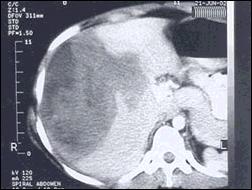

TAC abdominal: Imagen de masa intraparenquimal, aparentemente subcapsular en lóbulo hepático derecho de 14x8 cm sin calcificación en segmentos 5, 6, 7 y 8, sin dilatación de via biliar. Con el contraste se observa más hipodensa en relación a parénquima hepático (Fig. 2 y 3).

Fig 2.- TAC de Abdomen: Masa heterogénea en

segmentos hepáticos 5, 6, 7 y 8 de 14 x 8 cm.

Fig 3.- TAC de Abdomen: En la fase contrastada masa

hepática más Hipodensa en relación

al resto del parénquima.

Para el diagnóstico, cuenta el antecedente de ingesta de vegetales y/o agua contaminados y las formas de presentación como fiebre de origen desconocido, hepatitis granulomatosa, serositis, meningitis, cólico biliar o colangitis, dolor abdominal atípico, historia familiar de fasciolosis, e hipereosinofilia entre otros (4,10,15). Para la fase aguda, la presencia de fiebre, dolor en el hipocondrio derecho y eosinofilia, con una TAC y serología positivas son muy sugestivos de fasciolosis. Nuestra paciente acudió con un cuadro de fasciolasis en fase aguda dado por dolor en el hipocondrio derecho, hepatomegalia e hipereosinofilia, que en la evolución desarrolló un hematoma hepático, una complicación infrecuente que además tuvo una instalación atípica muy larvada, que pudo sospecharse con el apoyo de la radiografía de tórax mostrando elevación del hemidiafragma correspondiente y de la TAC abdominal revelando probable sangrado intrahepático. Ello permitió la descompresión quirúrgica. En el postoperatorio la hipereosinofilia persistente reforzó la posibilidad diagnóstica de fasciolosis la cual fue confirmada por serología. La fase crónica cursa con un cuadro clínico atenuado y suele confundirse con otras enfermedades (3,10).

El aporte de los estudios por imágenes es medianamente significativo, así la ultrasonografía puede mostrar lesiones hepáticas hipodensas/hipoecoicas que corresponden a los trayectos seguidos por las larvas, también puede revelar el parásito en la vesícula o vias biliares (4,7). La TAC puede mostrar en el parénquima hepático dos tipos de lesiones: Areas hipodensas nodulares de 1-10 mm únicas o más frecuentemente múltiples, o areas hipodensas como túneles de disposición radiada resaltadas con el contraste altamente sugestivas de fasciolasis, igualmente puede evidenciar la fasciola en las vias biliares (4,10). Los hematomas subcapsulares se ven como una zona hipoecogénica o compleja por la presencia de coágulos sanguíneos. En la TAC el sangrado es isointenso en relación al parénquima hepático normal pero con el contraste el tejido hepático normal aumenta su densidad. La sangre fresca intrahepática no se oscurece, por lo tanto se observa en forma hipodensa (6) como se muestran en el presente caso. La resonancia magnética nuclear puede sugerir granulomatosis hepática y proporciona hallazgos similares a la TAC. La gammagrafía demuestra múltiples defectos intrahepáticos en aproximadamente 50% de los casos (7).